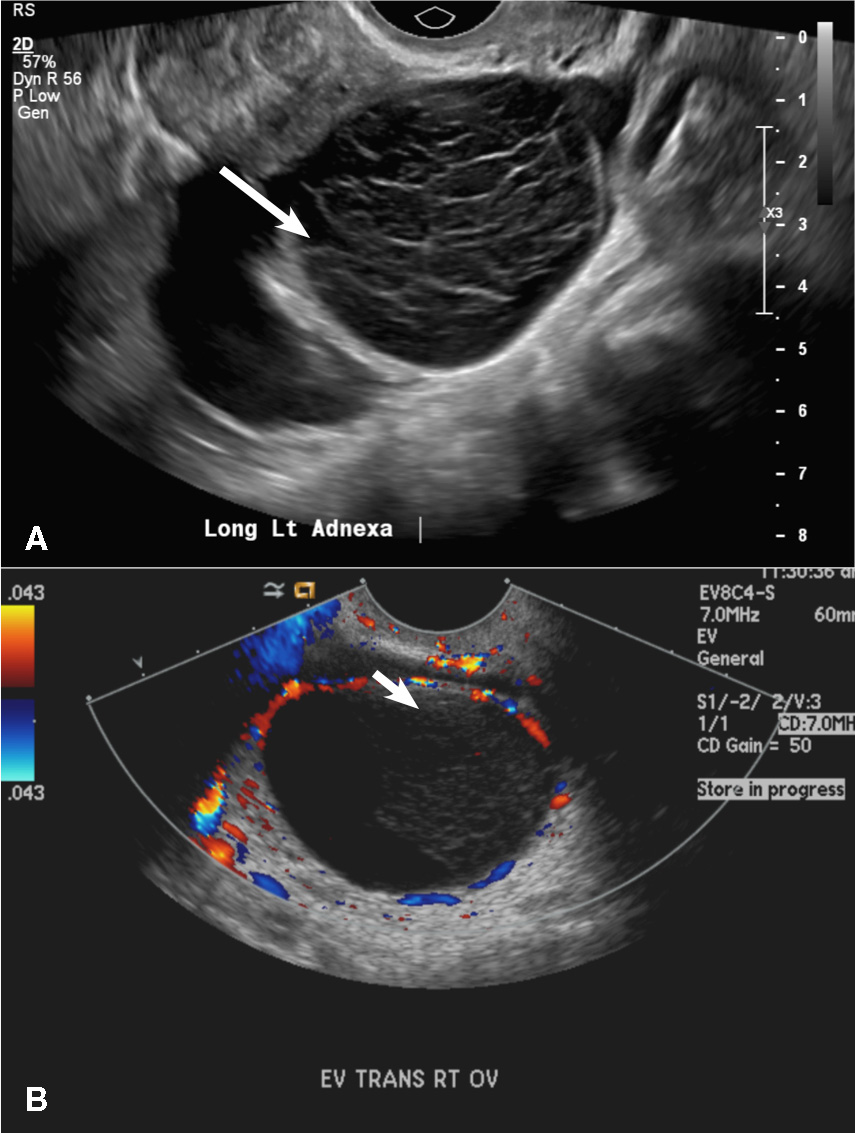

(B) Hemorrhagic cyst CORRECT

This type of cyst is well circumscribed and hypoechoic, with posterior acoustic enhancement and demonstrates a lacy reticular pattern of internal echoes due to fibrin strands (long arrow). The internal echoes also may be solid appearing with concave margins (short arrow) due to retractile hemorrhagic clot.1 The absence of internal vascular flow on color Doppler helps differentiate it from the solid components seen in ovarian neoplasm.

Hemorrhagic cysts. (A) Transvaginal pelvic ultrasound of the left ovary demonstrates a well-circumscribed hypoechoic cyst with posterior acoustic enhancement and demonstrates a lacy reticular pattern of internal echoes (long arrow). (B) Transvaginal pelvic ultrasound of the right ovary demonstrates a well-circumscribed hypoechoic cyst with solid appearing retractile hemorrhagic clot with concave margins (short arrow) and no vascular flow on color Doppler.